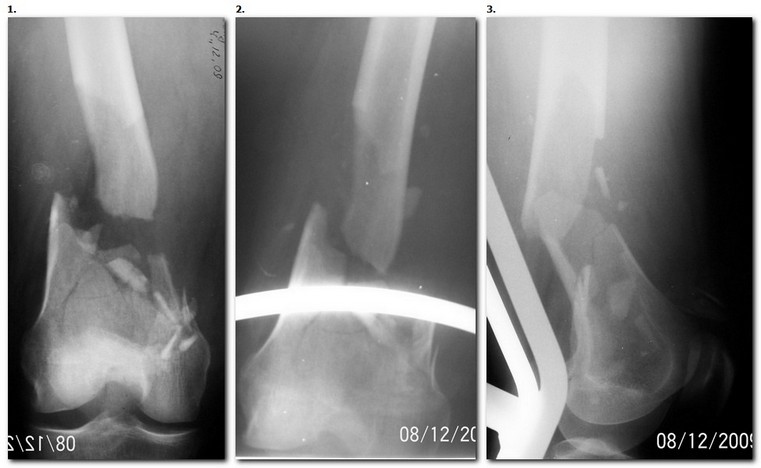

Уважаемые коллеги, возникли вопросы по тактике лечения перелома бедренной кости.

Пациентка через 3-е суток после автодорожной травмы - пассажир автомобиля. Имеется

открытый оскольчатый перелом н/3 правой бедренной кости. Создается впечатление о дефиците

костной ткани, рана до 5 см над надколенником, похоже фрагмент бедренной кости был

безвозвратно потерян при травме. Планируется ретроградный БИОС. Возникает вопрос об

обьеме и варианте костной пластики. Сопутствующий перелом в/3 обеих костей левой голени

сомнений по тактике не вызывает. Уважаемые коллеги, хотелось бы услышать ваши мнения по

данной ситуации. С уважением Николов О.В.